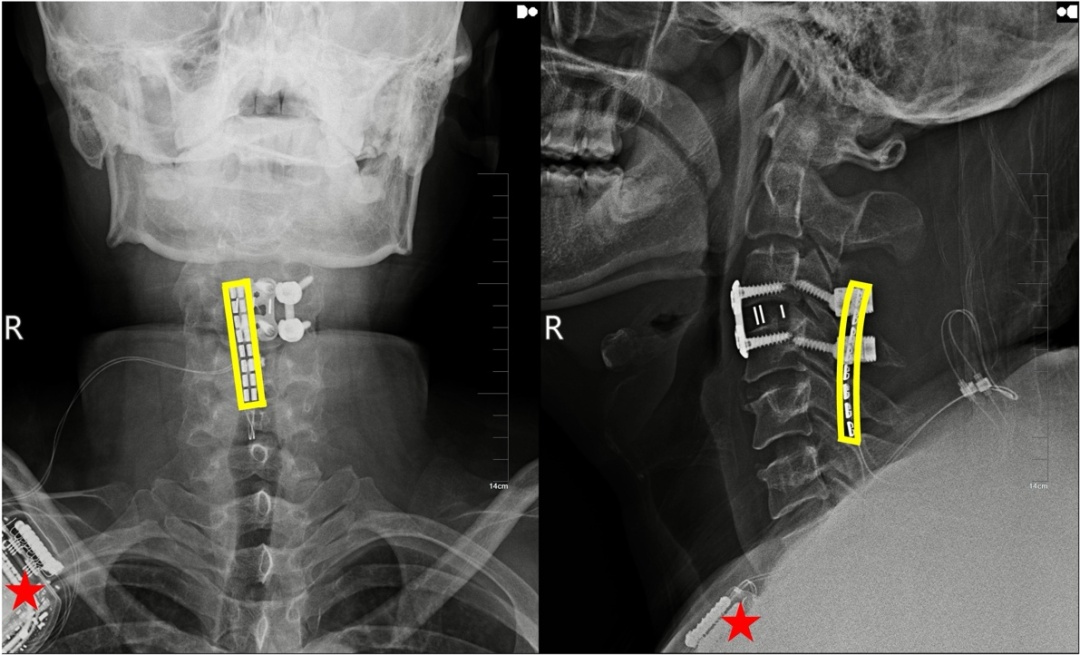

植入术后X线显示,黄色方框为电极位置,星号为皮下脉冲发射器位置